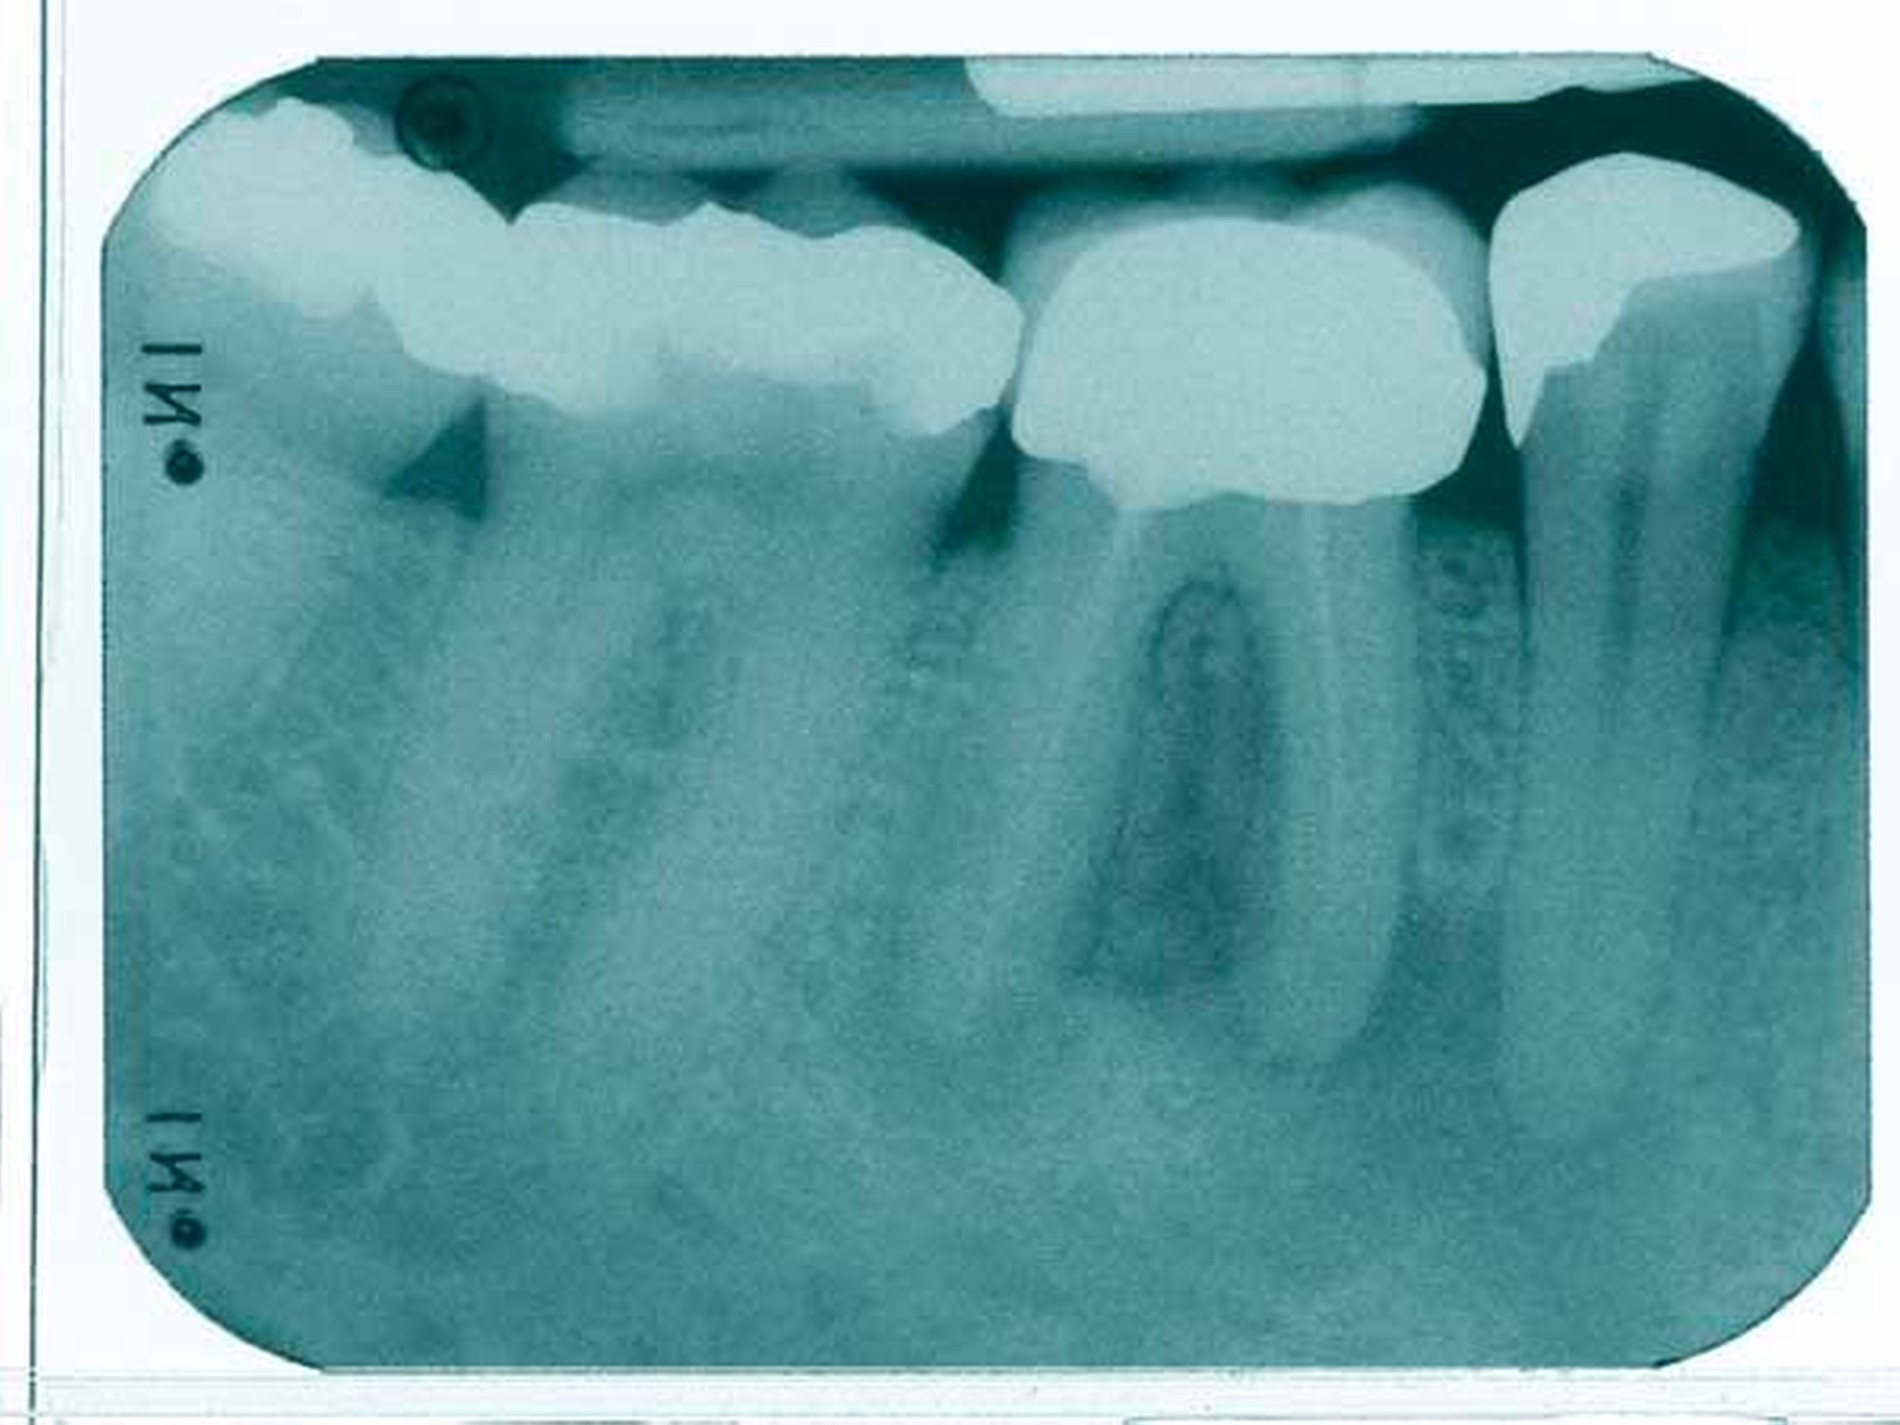

Der Fall: Cäcilia S. ist GKV-versichert. Nach ihrem berufsbedingten Umzug stellt sie sich im neuen Wohnort mit der Notwendigkeit einer Überkronung des Zahnes 24 in der Praxis von Dr. Peter B. vor. Der Befund ergibt ein suffizient konservierend versorgtes Gebiss mit einer Aufbaufüllung am zu überkronenden Zahn, der gemäß Anamnese auch endodontisch versorgt wurde. Ein mitgeführtes, etwa vier Jahre altes Röntgenbild, das vom früheren Zahnarzt der Patientin, Dr. Otto T., unmittelbar nach Abschluss der Wurzelkanalbehandlung angefertigt wurde, zeigt eine an beiden Kanälen bis ins letzte Drittel reichende, also den kassenzahnärztlichen Vorgaben entsprechende Wurzelfüllung.

B. beschließt, eine neue Röntgenaufnahme anzufertigen, auf der jedoch die Wurzelfüllung nur noch schwach erkennbar ist und im oberen Drittel der Kanäle endet. Auf Nachfrage gibt die Patientin an, sie habe für die Durchführung der Wurzelbehandlung nach aktuellem wissenschaftlichem Standard in einer deutschen Großstadt seinerzeit 250 Euro zuzahlen müssen. Zunächst zieht B. einen Mangel im Entwicklungsprozess seiner Röntgenbilder in Erwägung und fertigt unter sorgfältiger Abwägung eine weitere Aufnahme an, die aber den gleichen Befund zeigt. Daraufhin beschließt er, den vorbehandelnden Kollegen telefonisch zu kontaktieren. Der erklärt in diesem Gespräch, dass in seiner Praxis ausschließlich Calciumhydroxid zum Einsatz kommt. B. berichtet von der Resorption des Materials und gibt an, zunächst eine Revision durchzuführen, anschließend den Zahn lege artis abzufüllen und nach Ausheilung die prothetische Versorgung bei der Krankenkasse der Patientin zu beantragen, da nach den gegebenen Umständen eine Ablehnung des Antrags zu erwarten sei. T. antwortet daraufhin, dieses Problem habe er regelmäßig, würde es aber durch erneutes Einbringen von Calciumhydroxid und die zeitnahe Anfertigung eines Röntgenbildes umgehen: Mit der neuen Röntgenaufnahme habe es noch nie Probleme mit Krankenkassen im Zusammenhang mit beantragten prothetischen Versorgungen gegeben.